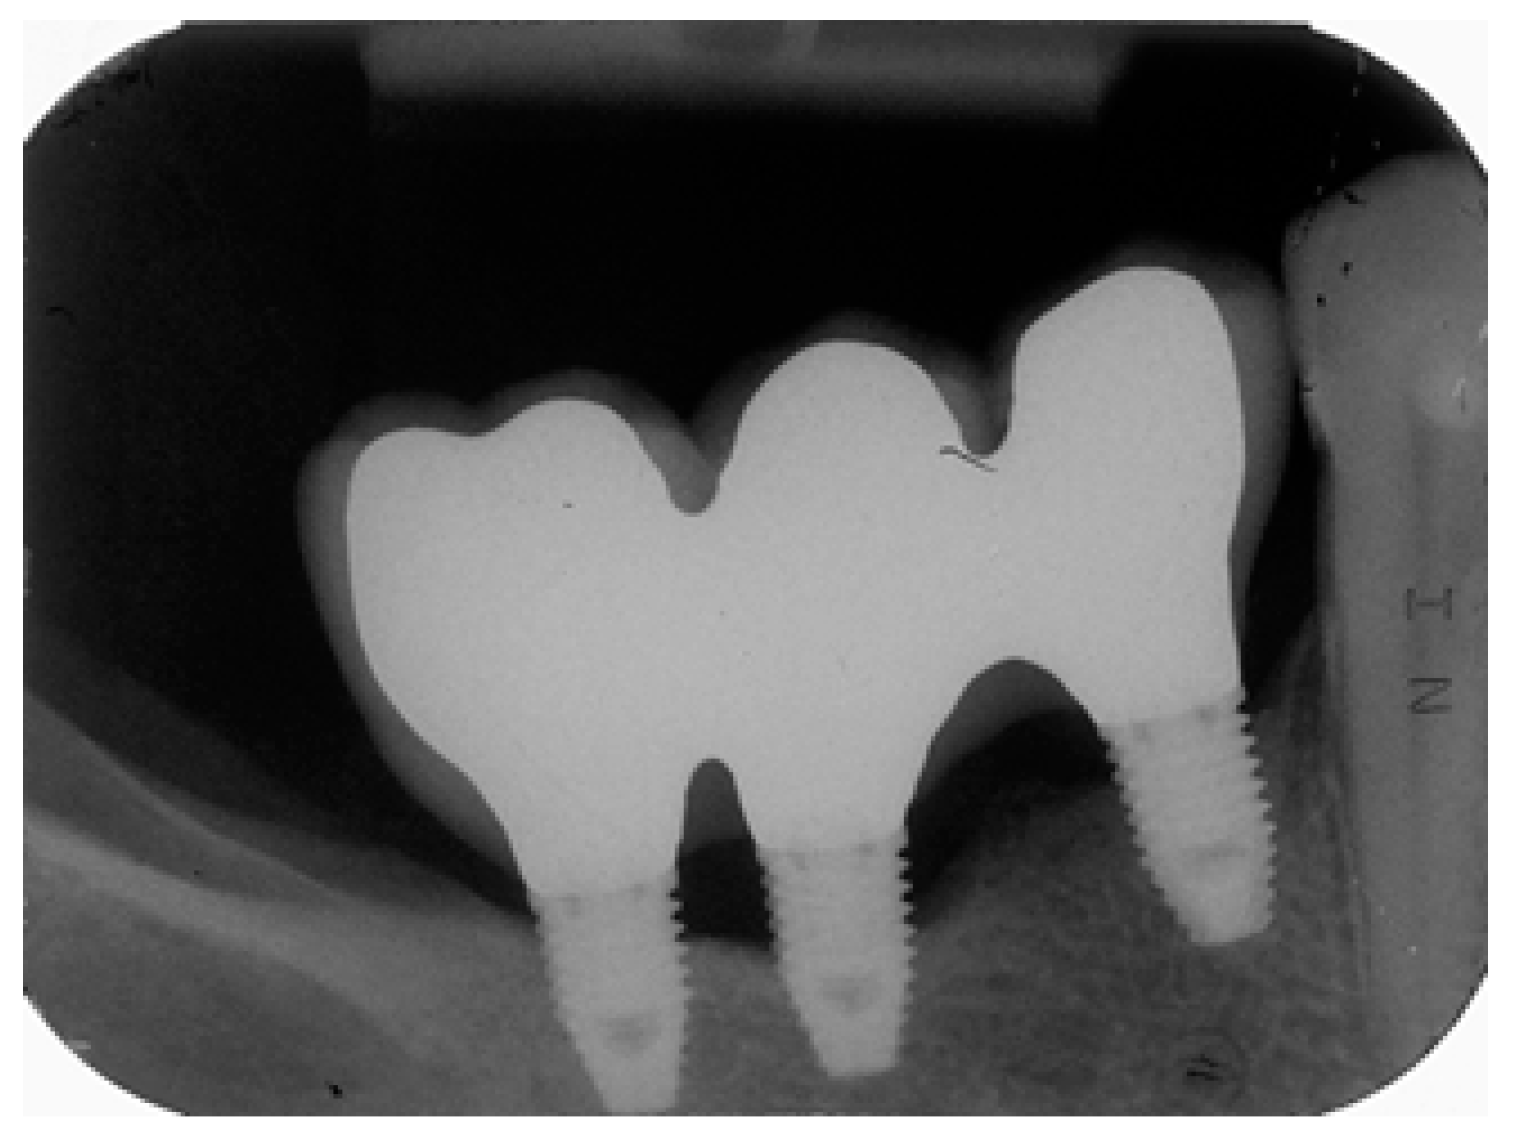

Risk scores are presented in Figure 2 and Figure 3. These scores can be used to obtain predictions for individual patients. As an example, we will examine a 59 year-old female with no history of periodontitis who was a non-smoker and who was rehabilitated with a three-unit implant-supported rehabilitation (three implants of 7 mm in length, positions #44–#46) that were restored using metal–ceramic material. At baseline (one year of follow-up) bacterial plaque and bleeding were present, and the bone level was located on the implants’ coronal third (Figure 2), which produces a total score of 8 points and puts her in the very high-risk profile. Peri-implant disease was diagnosed after 58 months on implant #45 due to the presence of peri-implant pockets of 5 mm and a three thread marginal bone loss (Figure 3).

Figure 3.

Periapical radiograph at 58 months of follow-up with peri-implant disease diagnosed in implant #45 with the presence of peri-implant pockets of 5 mm and a three threads marginal bone loss.